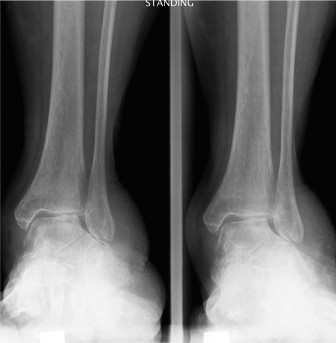

An 81-year-old female is brought to your office by her son. She has been treated for bilateral knee osteoarth…

A 65-year-old female with a history of osteopenia presents complaining of hindfoot pain for the past 2 years.…